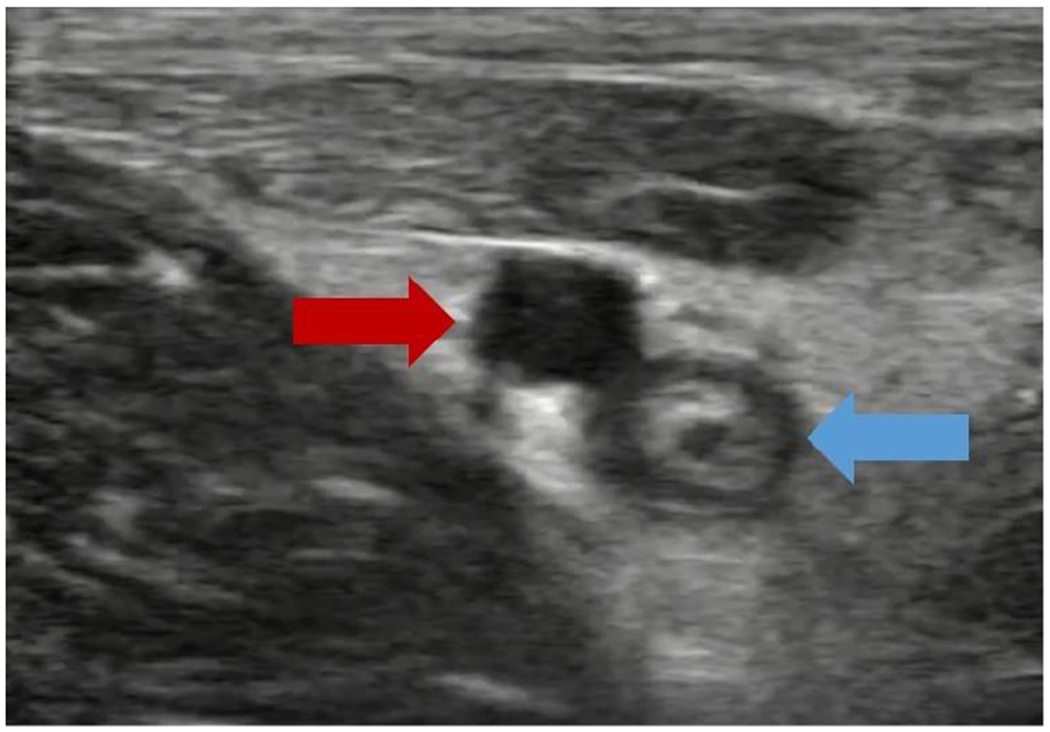

Figure 3: High Occlusion Ultrasound:

An ultrasound image of a one-week-old clot (4 days after catheter removal), exhibiting a high level of occlusion. The red arrow indicates the femoral artery, while the blue arrow indicates the clotted femoral vein.